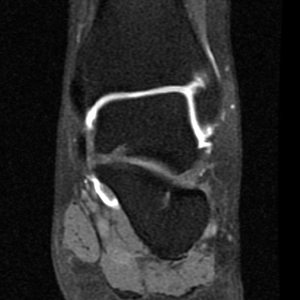

Ankle Arthrogram

Ankle MR Arthrogram

Arthrogram sequences of the ankle evaluate the talar cartilage and allow for staging of ostechondral defects of the talar dome. They can also better evaluate the joint capsule and its boundaries such as the anterior talofibular ligament.